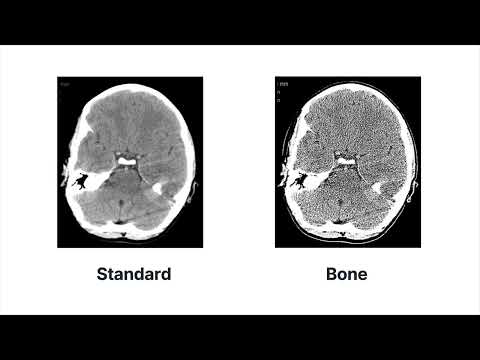

➡️ УЗНАЙТЕ БОЛЬШЕ: Этот видеоурок взят из нашего курса по получению изображений КТ. Перейдите по этой ссылке, чтобы ознакомиться с подробностями курса и дополнительными уроками. ➡️ О компании Clover Learning: Clover Learning — ведущий поставщик услуг онлайн-видеообучения, подготовки к сертификационным экзаменам и повышения квалификации для студентов и специалистов смежных специальностей в области здравоохранения и диагностической визуализации. Посетите наш сайт , чтобы получить доступ к сотням видеоуроков, тестов, вопросов для подготовки к сертификационным экзаменам и сертификатам о повышении квалификации. ➡️ ОПИСАНИЕ УРОКА: В этом уроке представлен обзор компонентов КТ-сканера, включая рентгеновскую трубку, детекторную матрицу, коллиматоры, генератор и аналого-цифровой преобразователь. В этом уроке также обсуждаются однородные и неоднородные детекторные матрицы. Цели: 1. Определить компоненты КТ-сканера. 2. Объяснить принципы работы однородных и неоднородных детекторных решеток. ➡️ ПРИСОЕДИНЯЙТЕСЬ К НАШЕМУ СООБЩЕСТВУ: / cloverlearning / cloverlearning.inc #cloverlearning #радиология #компьютернаятомография